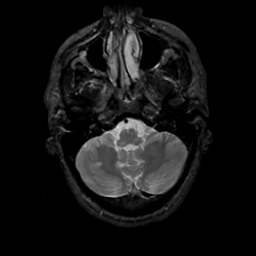

MR Study #4, March 3, 1991 -- Slice #9

[Home][Help][Clinical][Tour 1][Tour 2] Slice 9